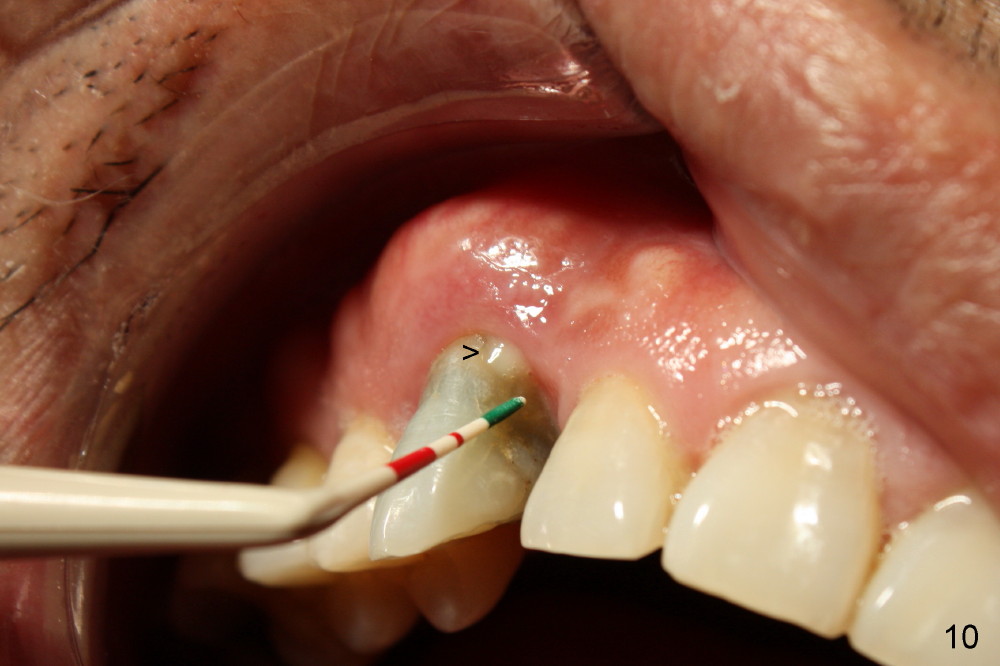

The tooth is discolored probably due to the side-effect of MTA(Fig.9; photo taken 9 months post-MTA).  The mesial gingiva recedes (*).  There is mild persistent pain with purulent discharge mesiobuccally (Fig.10 >).  The corresponding pocket remains 7-8 mm deep in spite of root canal therapy and MTA.